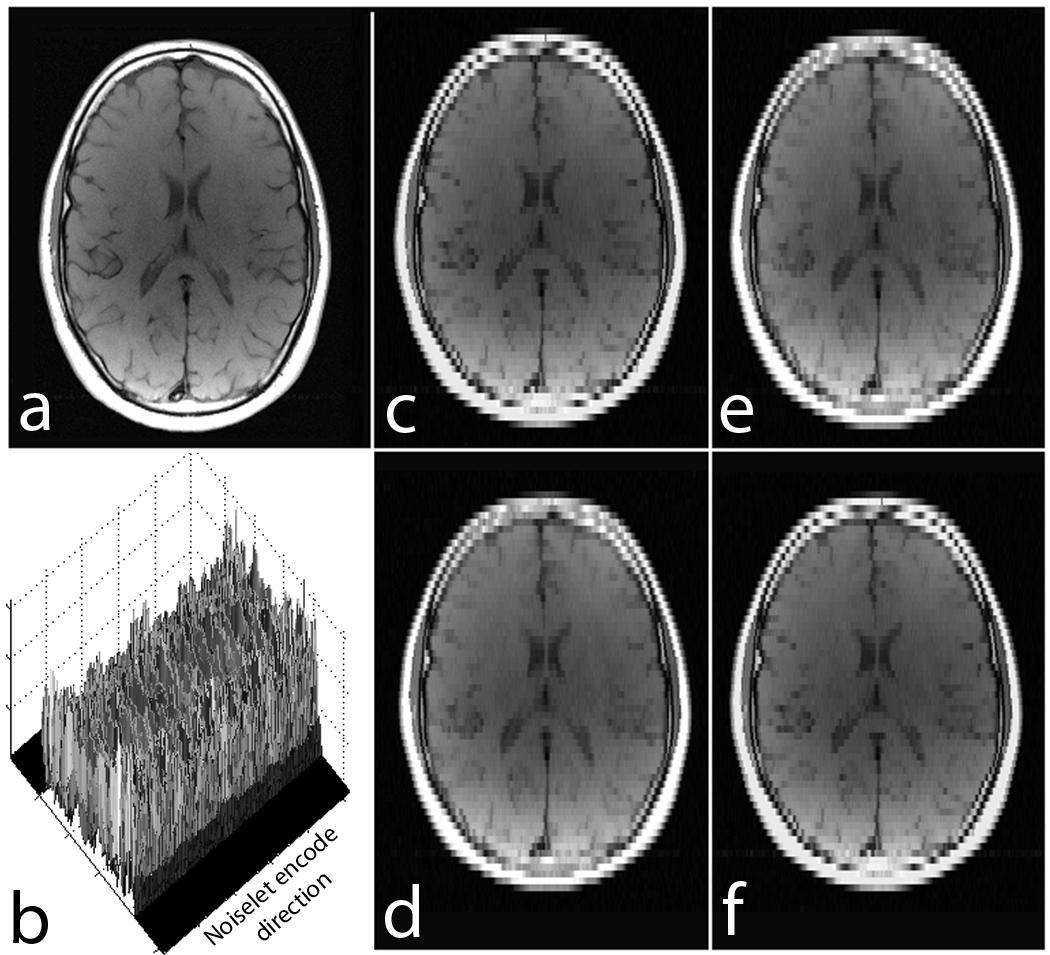

Refer to caption

Figure 5: Ref: represents the reference image 256×\times256 (up/down: phase encodes, left/right: frequency encode); (a)-(b): show images reconstructed using Fourier encoding with variable density random under-sampling patterns for acceleration factors of 2 and 3 respectively; (c)-(d): show images reconstructed using noiselet encoding with completely random under-sampling patterns for acceleration factors of 2 and 3 respectively. Noiselet encoded CS-MRI performs better than the Fourier encoded CS-MRI when completely random under-sampling is used for both the encoding schemes. This is due to the better incoherence provided by the noiselets. However, noiselet encoding with a random under-sampling pattern performs similar to Fourier encoding with a variable density random under-sampling pattern.

Fig. 5 show the images reconstructed with Fourier encoding and noiselet encoding using variable density random under-sampling and completely random under-sampling pattern respectively. The noiselet encoded CS-MRI performs similar to that of the Fourier encoded CS-MRI. This is due to the fact that in the case of variable density random under-sampling, the Fourier encoding judiciously exploits extra information about the data, namely the structure of k-space. The center of the k-space data has maximum energy and hence, by densely sampling the center of k-space, the Fourier encoding captures most of the signal energy and results in better performance.